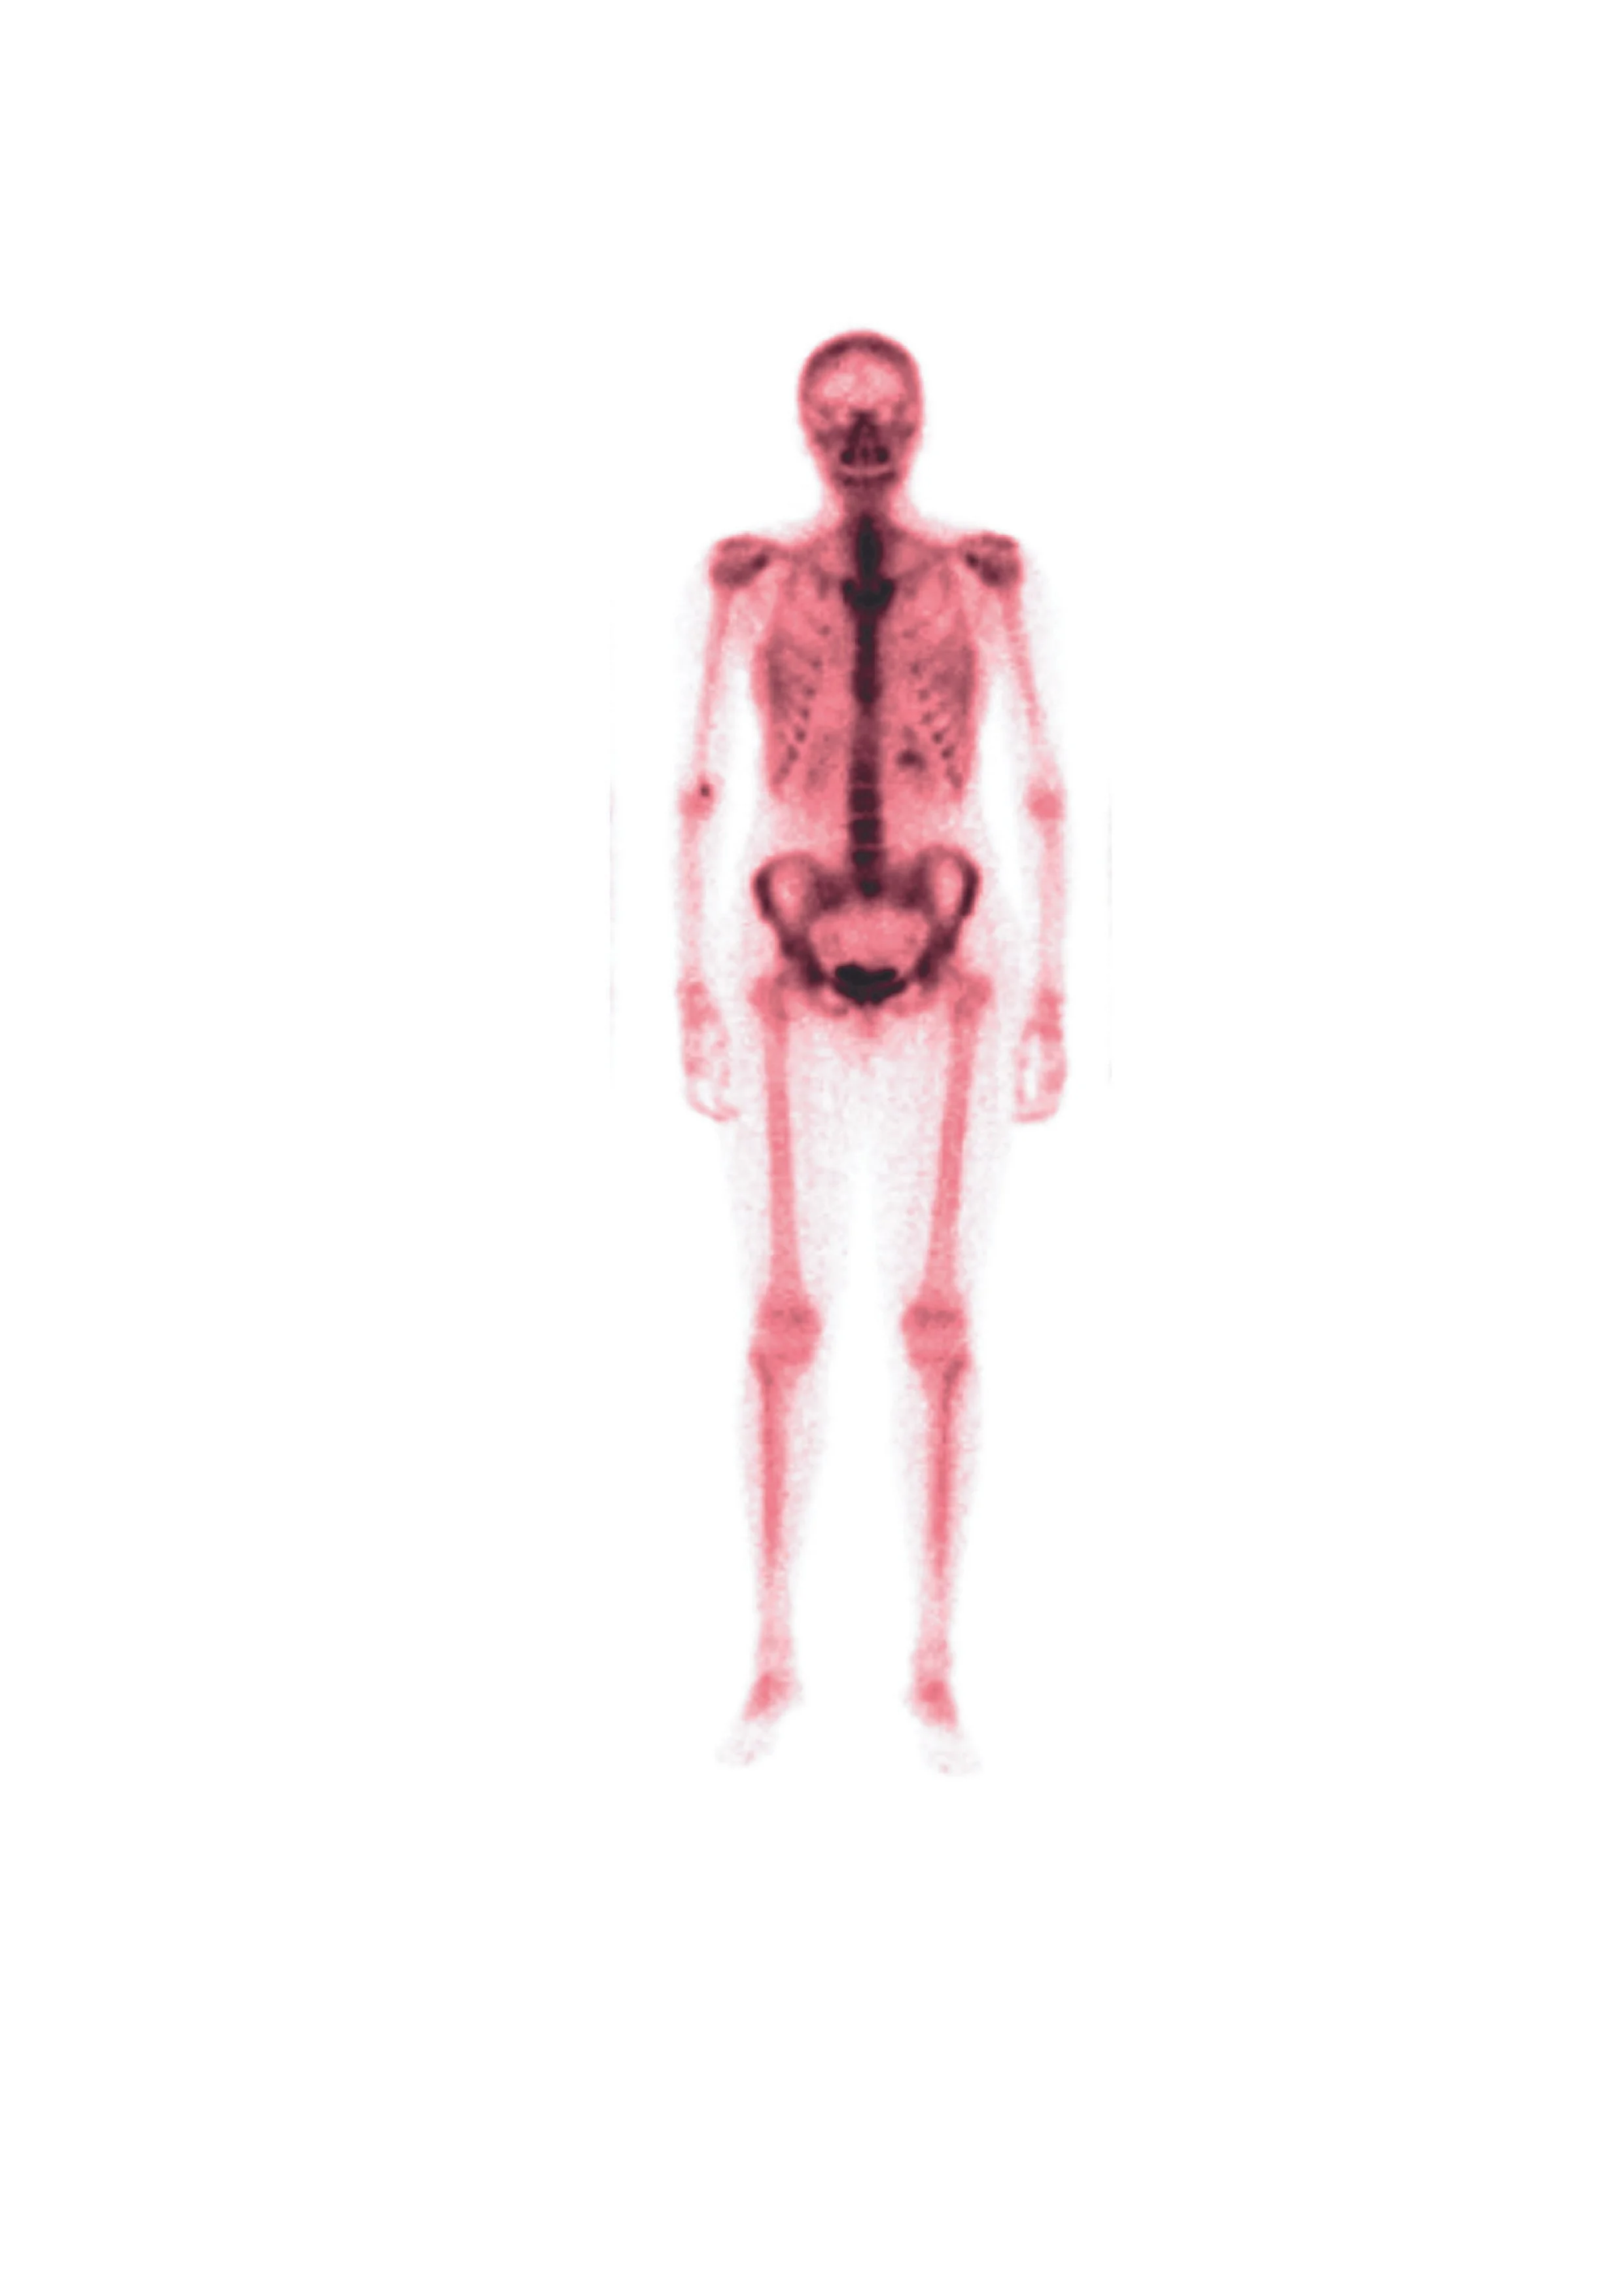

Confessions of a Bad-Backed Young Masc